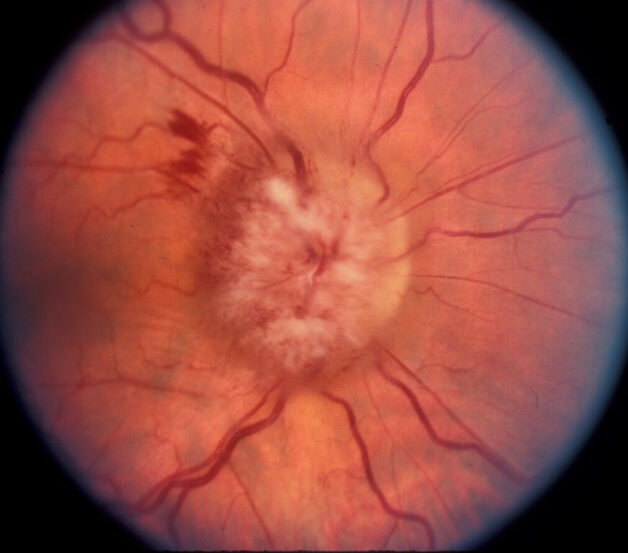

ONTT cũng phát hiện ra rằng trong số 389 bệnh nhân không được chẩn đoán mắc MS xác định hoặc có thể xảy ra trên lâm sàng khi bắt đầu nghiên cứu, nhóm dùng steroid tiêm tĩnh mạch cho thấy tỷ lệ phát triển MS xác định trên lâm sàng thấp hơn trong vòng 2 năm đầu (7,5%) so với nhóm dùng giả dược ( nhóm 16,7%) hoặc nhóm prednisone (14,7%). Hầu hết tác dụng có lợi này được thể hiện ở những bệnh nhân có kết quả chụp cộng hưởng từ (MRI) ban đầu bất thường gợi ý tổn thương mất myelin nhưng tác dụng bảo vệ rõ ràng này không được duy trì sau 3 năm. Các kết quả MRI ban đầu bất thường cho thấy 1 hoặc nhiều tổn thương mất myelin điển hình được chứng minh là yếu tố tiên đoán mạnh nhất cho sự phát triển của MS lâm sàng trong 15 năm tiếp theo (nguy cơ khoảng 72%). Trong số những bệnh nhân viêm dây thần kinh thị giác có kết quả MRI não cơ bản bình thường, có 05 đặc điểm được xác định là không có nguy cơ mắc MS: không nhận thức được ánh sáng( ST-), không đau, phù đĩa thị nặng, phù đĩa thị xuất huyết và xuất tiết võng mạc.